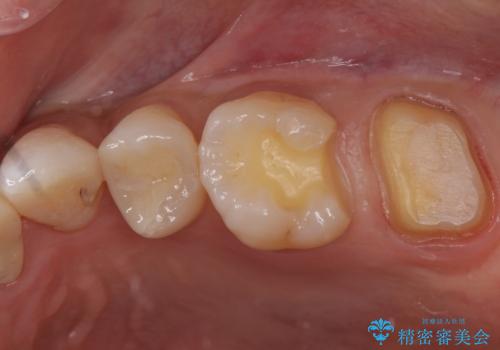

- 矯正後の虫歯治療です。

初めは一番奥の歯の樹脂の詰め物のやり替えをする予定でしたが、予想よりも歯の厚みが取れなかったため破折リスクを抑えることを目的にクラウンで修復処置を行いました。

その際手前の歯にも虫歯が確認されたため、こちらはインレーでの修復処置を行いました。